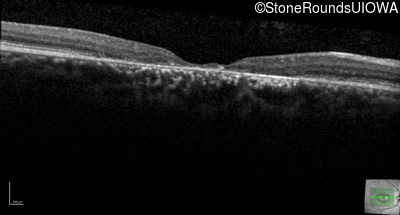

AR Stargardt Disease (IIA)

Age at visit: 29 years

This 29-year-old man had good vision until his early 20's. at which time he began to experience a slow reduction in his acuity. His driver's license was restricted at age 27.

Age at visit: 29 years (Visit 2)